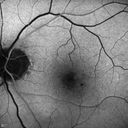

Microaneursyms and Macular Edema Not Diabetic

85 year old man has been tested about 2-3 times and is always negative for diabetes

Microaneurysm - NOT npdr - Probably Hypertensive